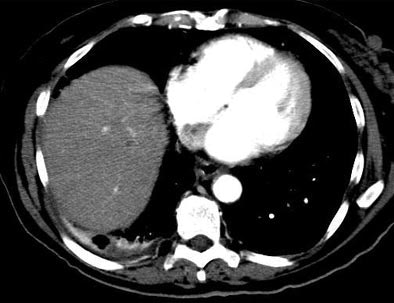

| Another patient with fever after prolonged neutropenia. Above, arterial-phase CT shows a type 2b lesion (arrow). Below, portal-venous phase fails to show a lesion. |

The group performed a phase-based analysis of 536 liver lesions assessed in 36/60 positive studies. Arterial-phase CT identified all 36 (100%) of the positive livers, whereas the portal-venous-phase studies were positive in only 23/36 (69%) of the studies (p<0.001).

"On the lesion-based analysis, arterial-phase (CT) identified 90% (483) of 536 lesions assessed," Metser said, whereas portal-venous-phase CT identified 69% (329/536, p<0.001), and noncontrast CT 57% (265/465, p<0.001), he said. Focal liver lesions were graded as more conspicuous on arterial-phase and non-contrast CT compared to portal-venous phase.

The most marked difference between arterial and portal-venous phase CT could be seen in the detection rate for the hyperdense type 4 lesions, he said. On arterial-phase CT nearly 80% of the lesions had strong enhancement patterns suggestive of infection. Meanwhile, only 40% of the lesions on portal-venous phase CT had such a pattern, and only 45% of the type 4 lesions that could be seen on portal-venous phase CT had such a pattern.